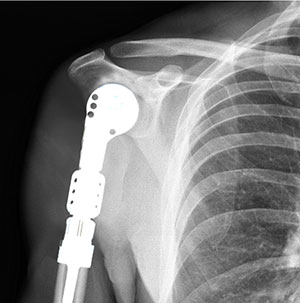

• Partial Shoulder Replacement

Partial shoulder replacement, also called shoulder hemiarthroplasty, is a surgical procedure...